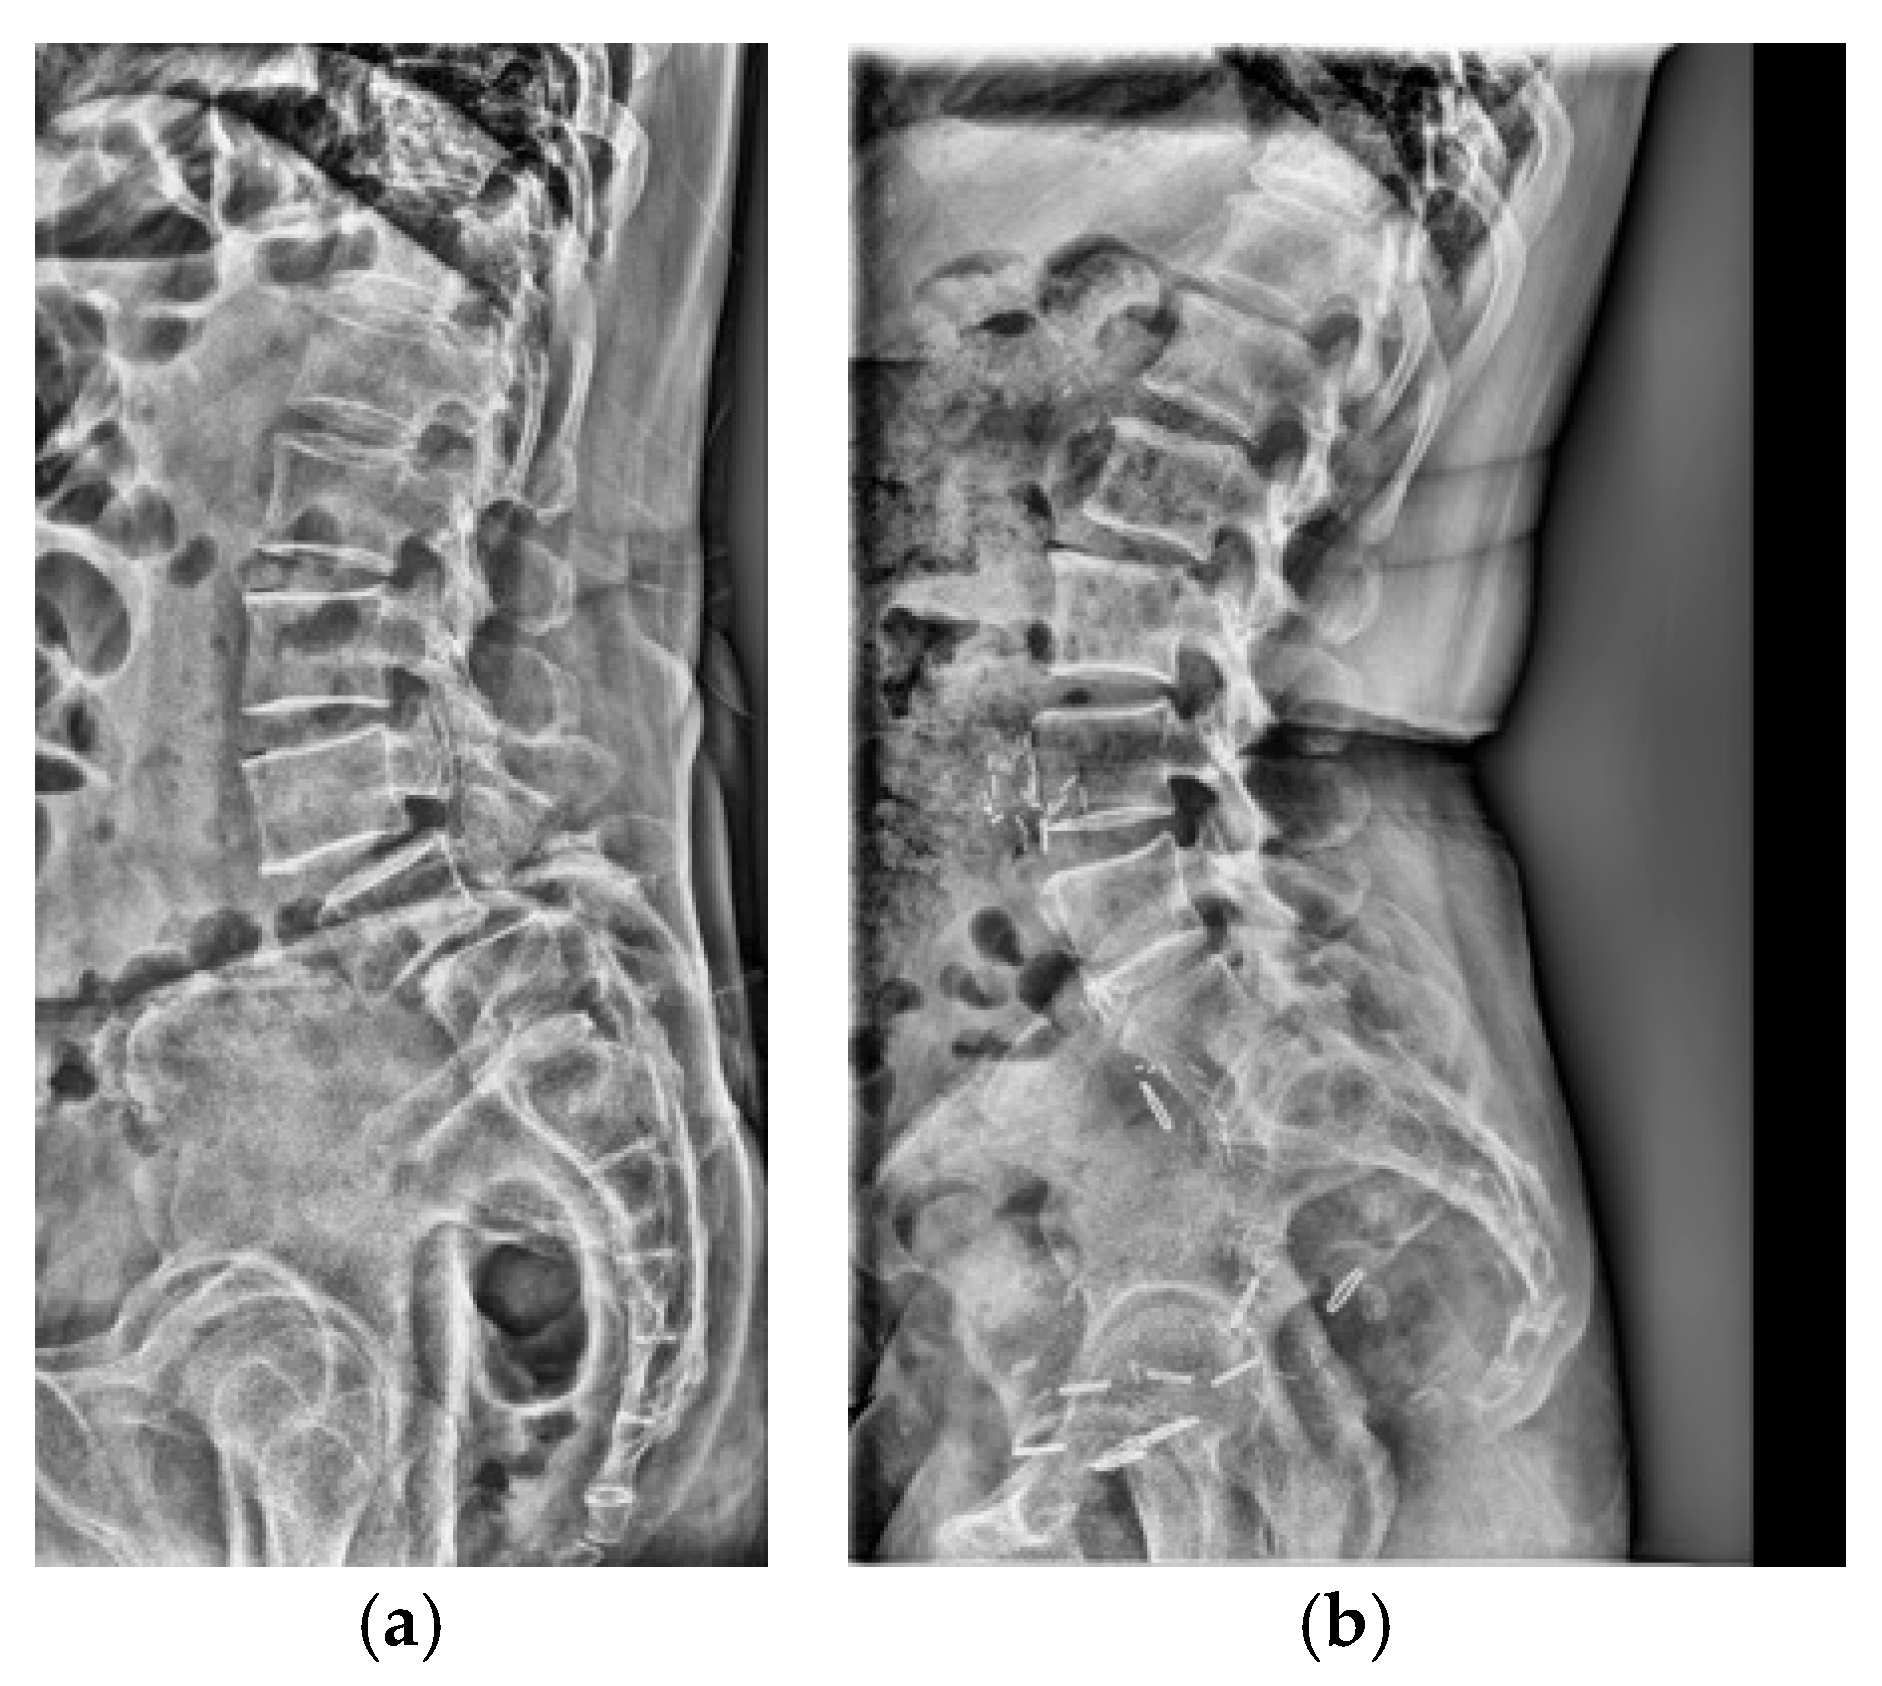

Adult patients (≥18 years) who underwent standing lumbar lateral radiography at a single tertiary hospital between January 2010 and November 2023 were included for this retrospective study. All standing lumbar lateral radiographs were acquired using digital radiography systems from multiple manufacturers, including Philips Healthcare (Amsterdam, The Netherlands), Canon Medical Systems Corporation (Ōtawara, Tochigi, Japan), Samsung Electronics Co., Ltd. (Suwon, Republic of Korea), and Fujifilm Corporation (Tokyo, Japan). To establish a definitive ground truth, only patients for whom the presence or absence of LSTV could be unequivocally determined using whole-spine MRI, CT, or radiographs that allowed for accurate vertebral enumeration were selected. The presence or absence of LSTV was labeled based on the MRI conclusion that explicitly mentioned transitional vertebra, lumbarized, sacralized, lumbarization, or sacralization. Patients were excluded if they had a history of lumbar surgery with instrumentation, severe spinal deformities or pathologies obscuring local anatomy, or poor image quality (Figure 1a). The final dataset was stratified, with 10% reserved as an independent test set and the remaining 90% subjected to stratified 5-fold cross-validation for model development and validation. Representative examples of each class are shown in Figure 1b,c, illustrating the visual differences between LSTV cases and normal lumbosacral anatomy. These examples highlight the morphological variability that makes manual identification challenging.

After applying the inclusion and exclusion criteria, the final dataset comprised 3116 standing lumbar lateral radiographs. Of these, 1941 (62.3%) were diagnosed with LSTV and 1175 (37.7%) were classified as normal. The dataset was divided into a training set (n = 2803) and an independent test set (n = 313). There were no significant demographic differences between the two sets.

Figure 1. (a) Flow diagram of patient selection and dataset partitioning. Adult patients (≥18 years) with standing lumbar radiographs and MRI/CT-confirmed LSTV were included (n = 3116; 1941 LSTV, 1175 normal) and divided into training (n = 2803) and independent test (n = 313) sets. (b) Representative lateral radiograph showing LSTV with lumbarization of the S1 vertebra and morphological alteration of the L5–S1 junction. (c) Representative radiograph of a normal lumbar spine illustrating a well-defined lumbosacral junction and distinct separation between the L5 vertebra and sacrum.